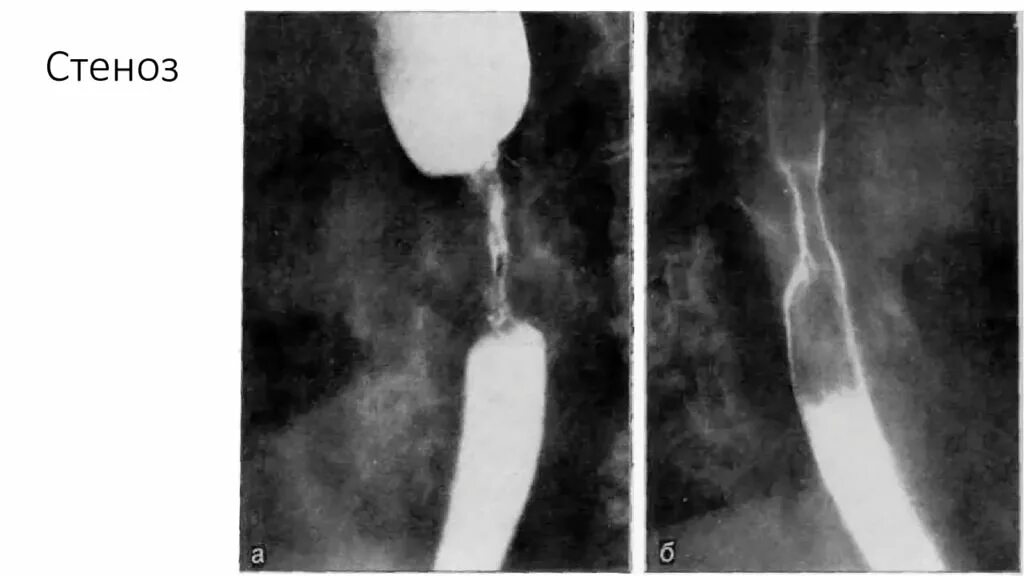

Стенозирующее образование